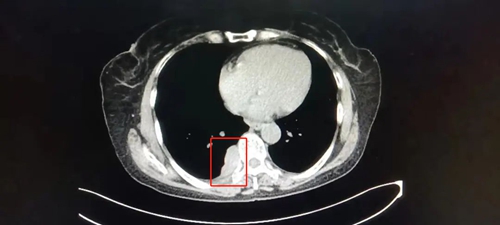

患者陈女士,59岁,因右侧胸背部疼痛半个月来我院就诊,经检查,胸部Ct结果显示:T8椎体旁紧贴胸膜处占位病变,且气管有先天畸形改变。陈女士既往有冠心病、高血压病和甲亢病史,家庭贫困。考虑其家庭状况,经充分术前评估,主管医生葛庆升详细告知陈女士病情及诊疗方案后,陈女士及其家属反复思量要求在家乡医院进行手术治疗。在郑州大学第二附属医院苏彦河教授的技术指导下,胸外科团队制定了周密的诊疗方案,因无法为陈女士完成单肺呼吸麻醉,经麻醉科会诊后,决定对其施行人工气胸胸右侧胸腔镜下纵膈肿瘤切除术,人工制造气胸,在纵膈中自下向上极度精准的操作,切除肿瘤。手术过程十分顺利,术中几乎无出血,术后患者恢复良好,现已康复出院。

![]() ![]() (术前CT) | ||